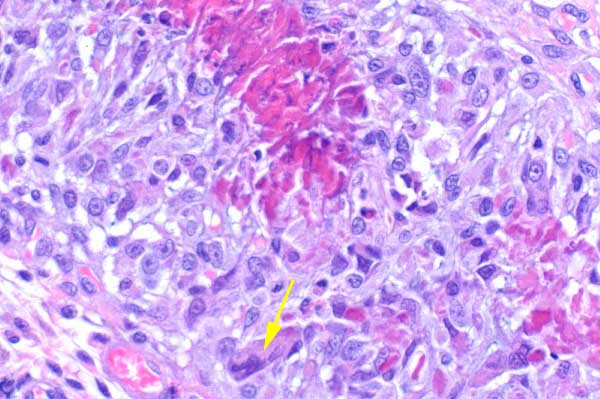

These foci are surrounded by abundant macrophages (sometimes forming multinucleated giant cells (arrow)), eosinophils, neutrophils, lymphocytes and mast cells.